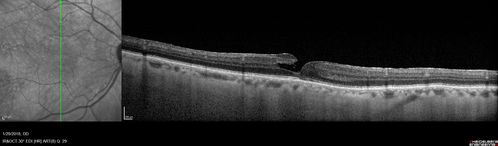

Hemangioma OS with good vison - 01-29-18

Images 7 years following initial uploaded images

Sturge-Weber Encephalotrigeminal Angiomatosis